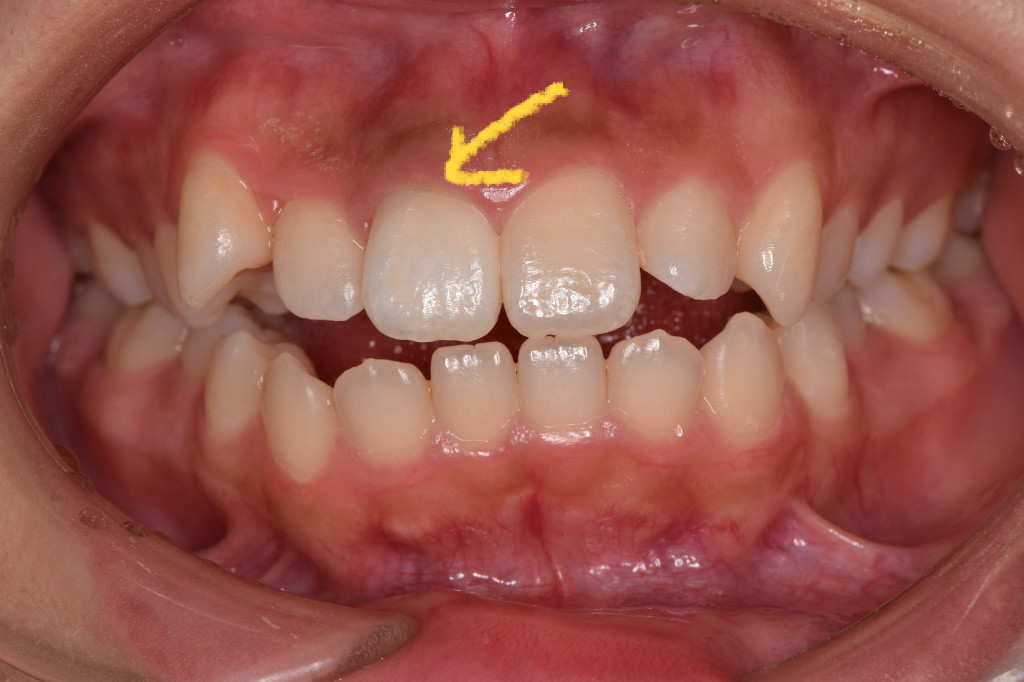

そこで、歯の裏から漂白する薬剤をいれること、1週間後。

こんなに綺麗に白くなりました。